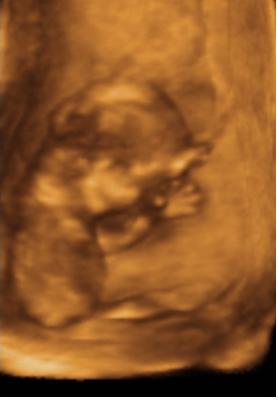

26 hetesen2007.12.13 20:04